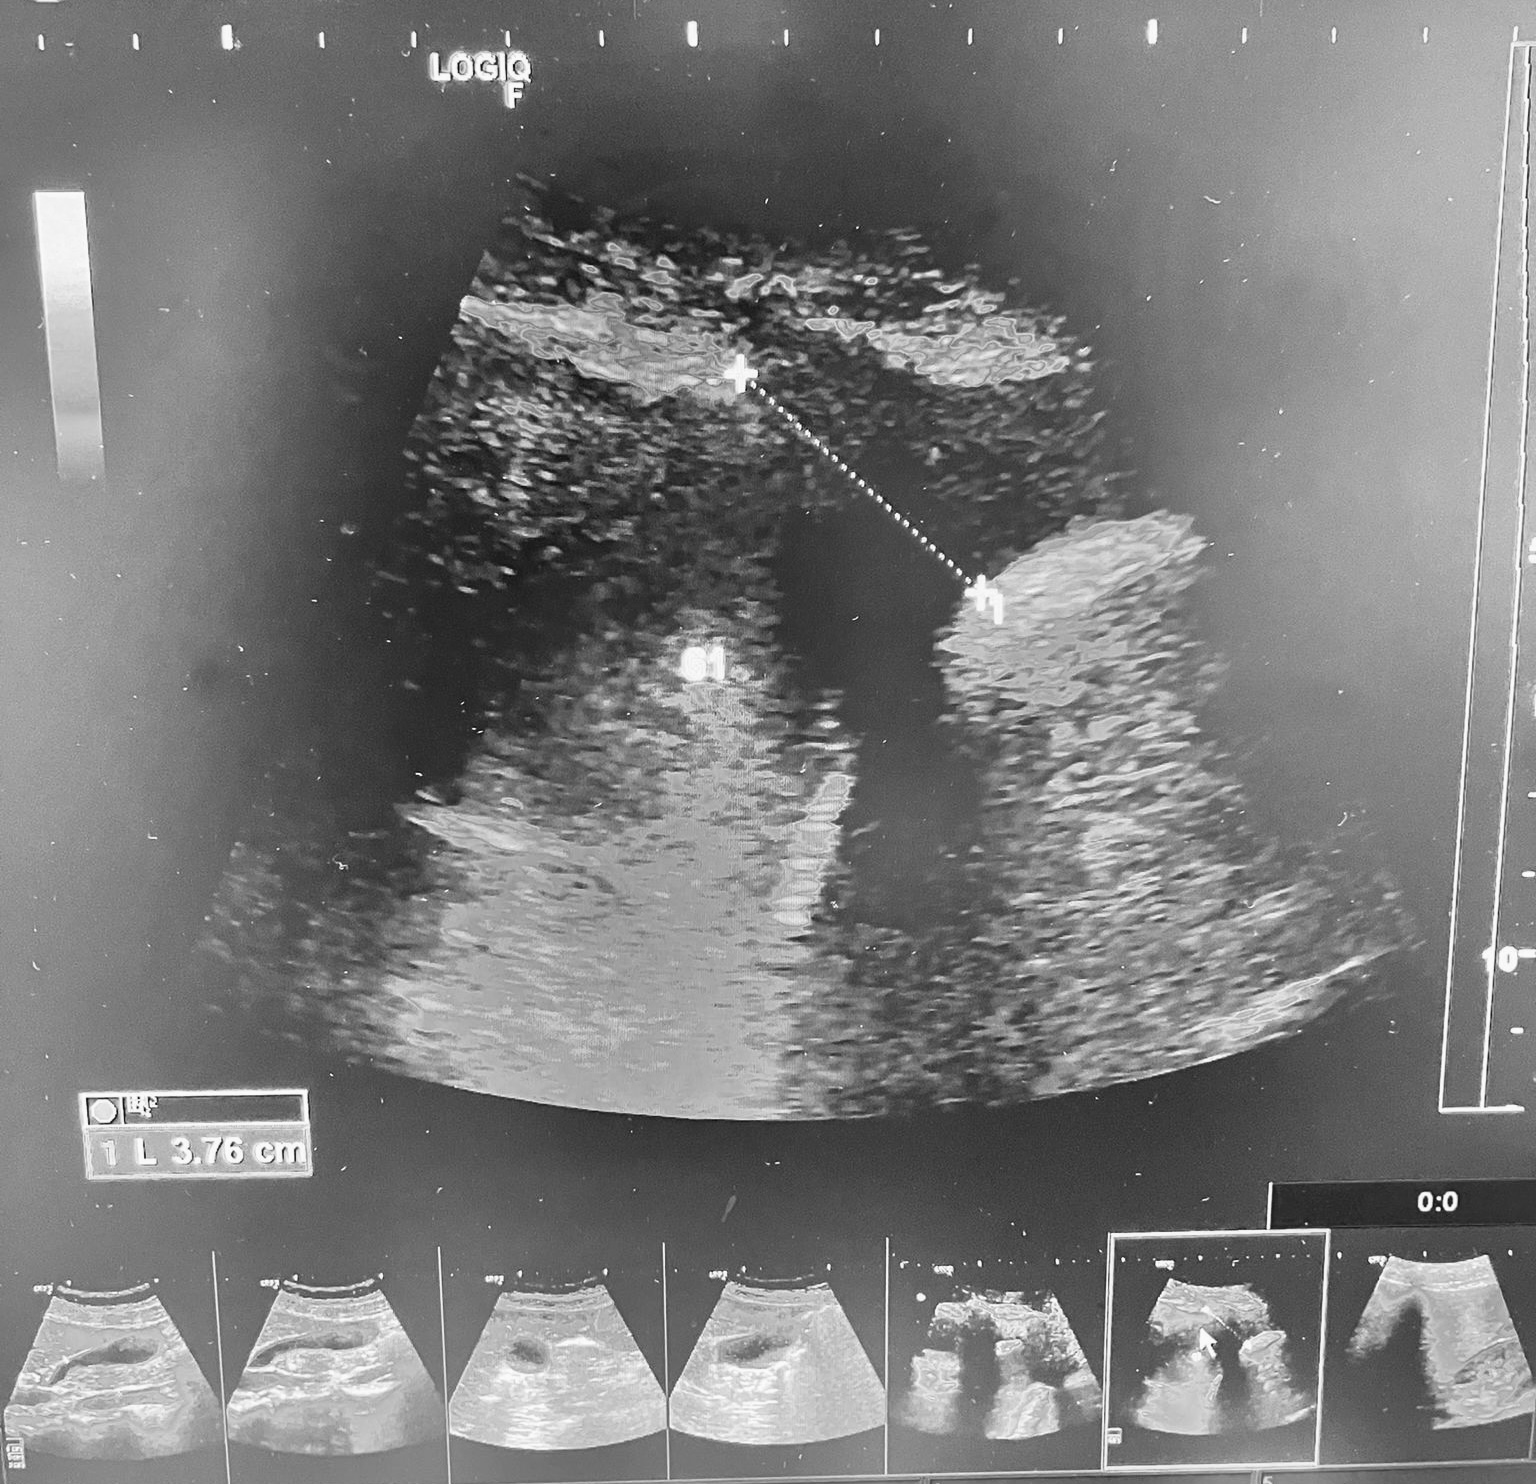

Hallazgos ecográficos

ECO pulmonar: gran derrame pleural unilateral izdo con «signo de la medusa» presente, cuantificamos 740 ml de liquido pleural.

Asimismo en base derecha, visualizamos múltiples confluencias de líneas B.